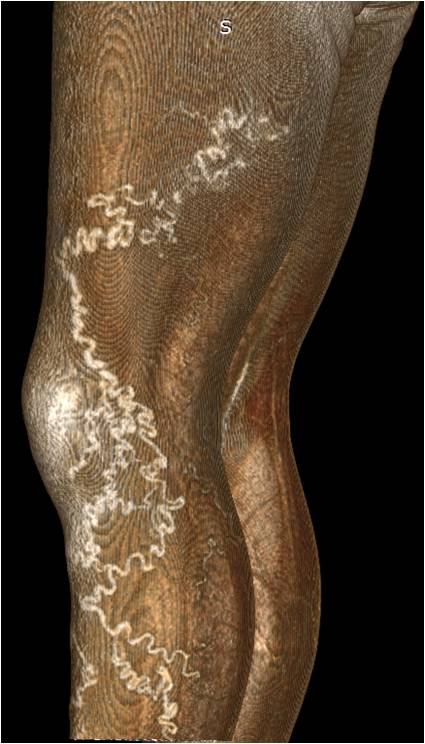

Patient A., 45 years old. Diagnosis: The left lower limb varicose vein disease, CEAP class C2. The disease had been present for about 10 years and was associated by the patients with physical labor. No edema. The volume of the right lower leg corresponds to that of the left lower leg (Figure 5).

CT-phlebography: deep and superficial veins uniformly, homogenously contrasted along the entire length. Along the posterolateral thigh surface, varicose transformation of saphenous veins associated through the PV with the deep femoral vein (Figures 6, 7).

Fig. 6. Patient A., 45 years old. Computer phlebogram, 3-D reconstruction mode. Varicose saphenous veins along the posterolateral surface of the thigh and lateral surface of the shin

Fig. 7. Patient A., 45 years old. Computer phlebogram, multiplanar reconstruction mode.

Notes: 1 — common femoral vein, 2 — deep femoral vein, 3 — perforating vein associated with varicose veins, 4 — varicose saphenous veins.